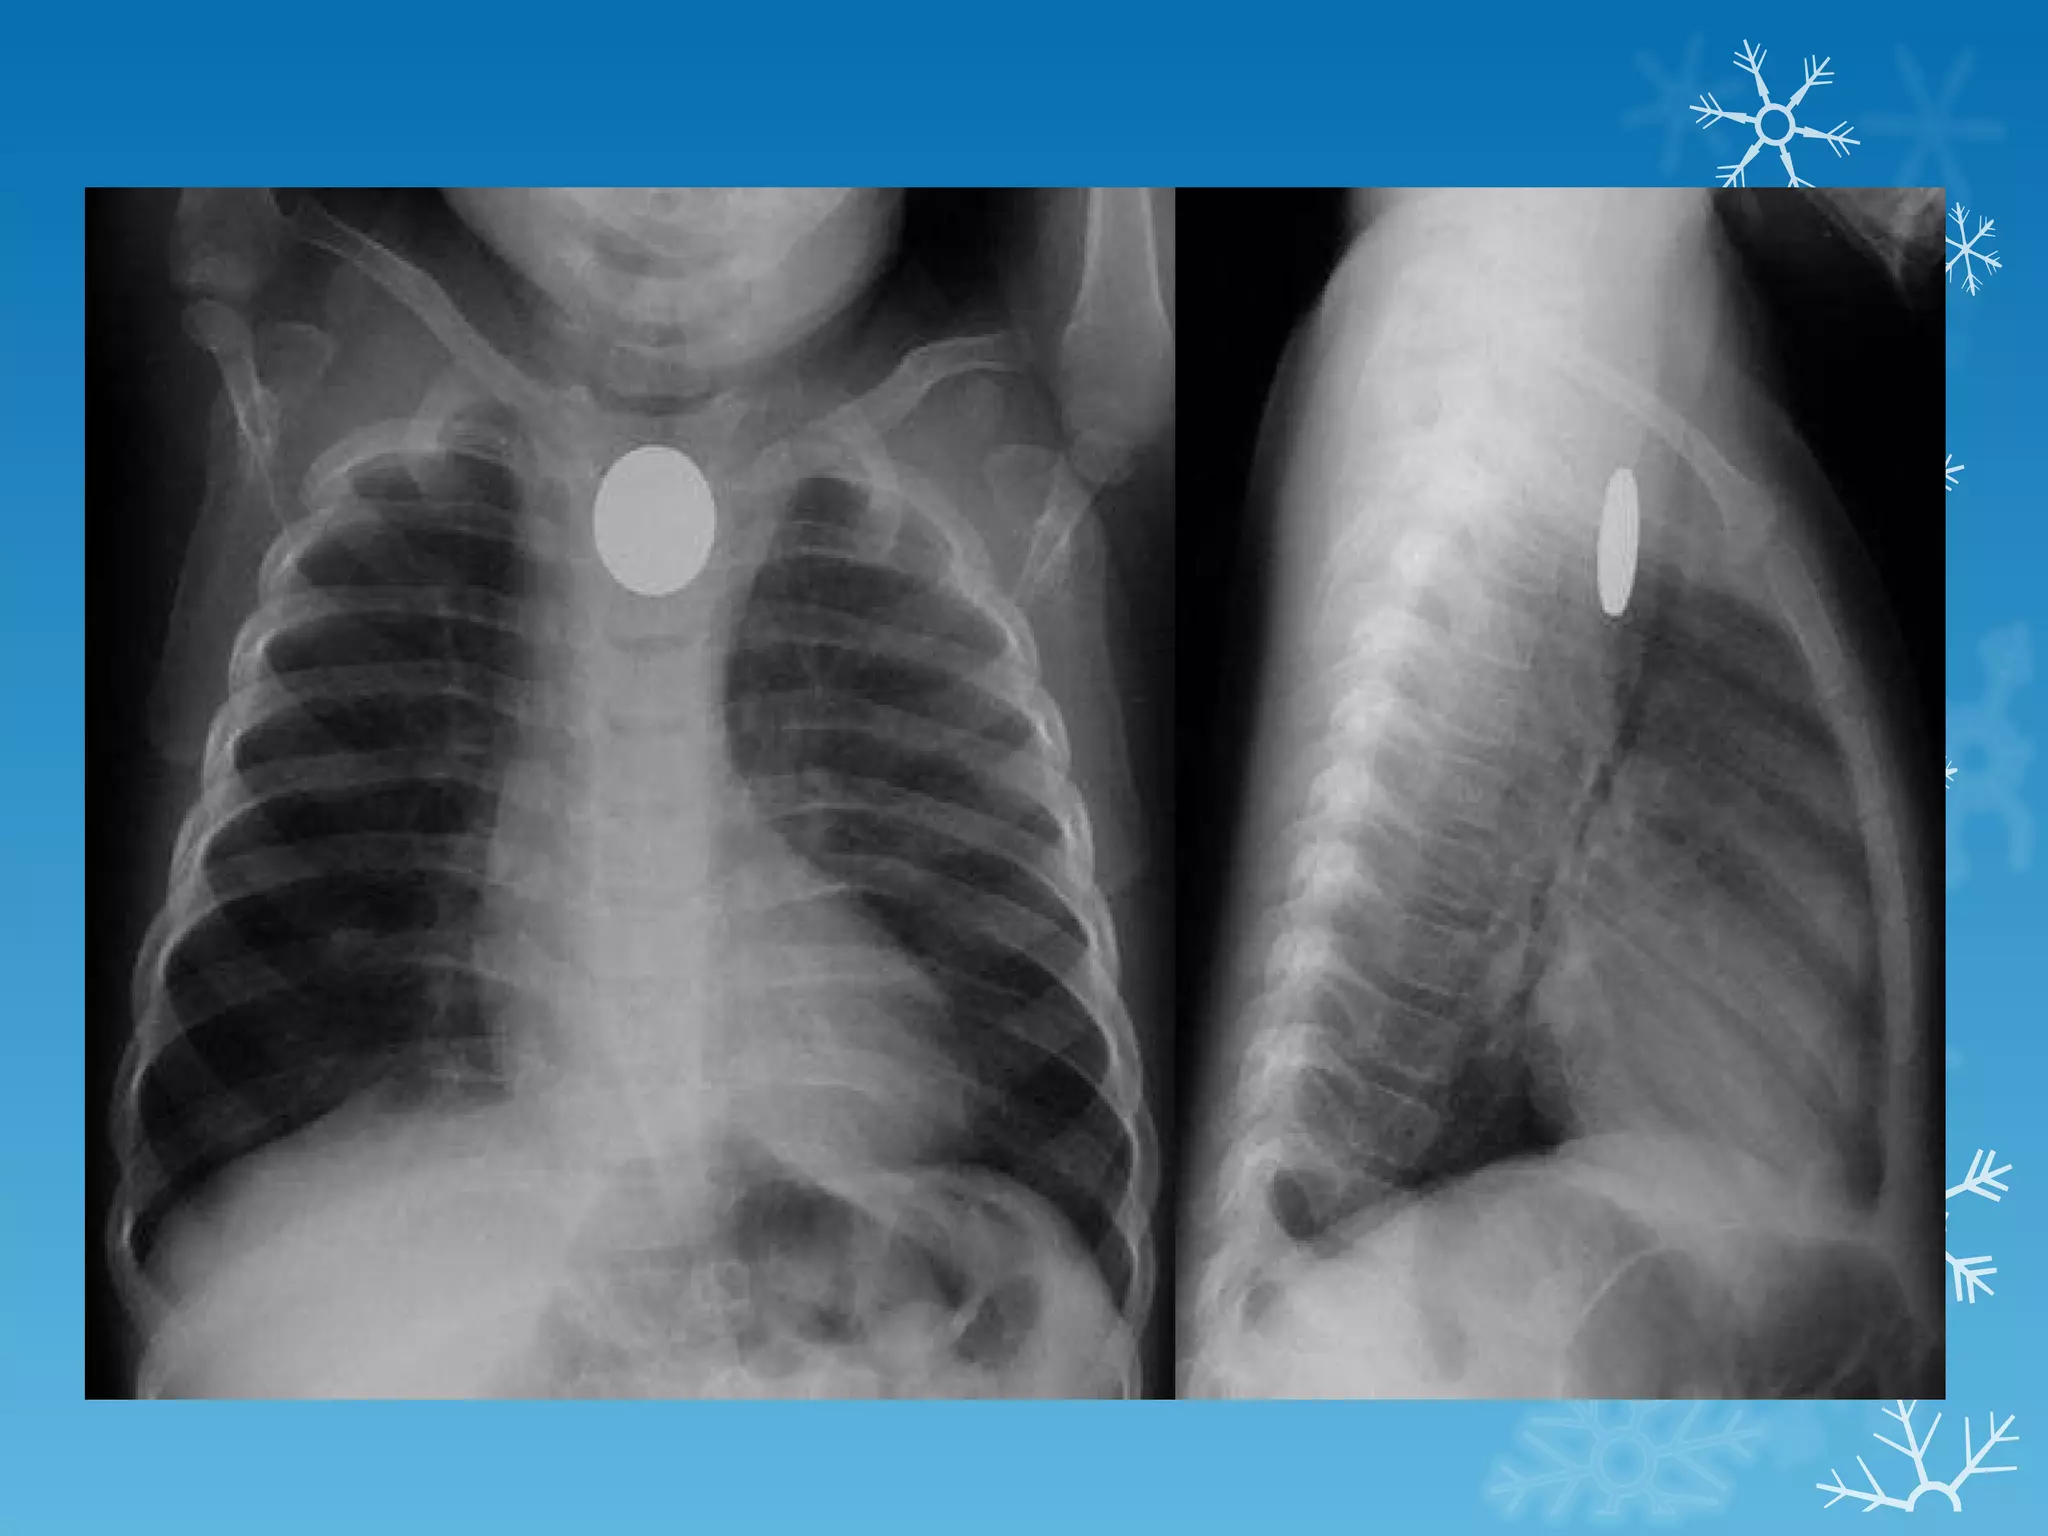

This document discusses chest x-ray interpretation and provides guidance on evaluating x-rays. It explains that tissue density determines how an x-ray beam penetrates, with denser tissues appearing whiter and less dense tissues appearing blacker. It also outlines different chest x-ray views and factors to consider like patient orientation, age, gender, and rotation. Abnormalities are described as appearing too white, too black, too large, or in the wrong place. The document stresses a systematic approach of identifying, localizing, describing lesions, and providing differential diagnoses.